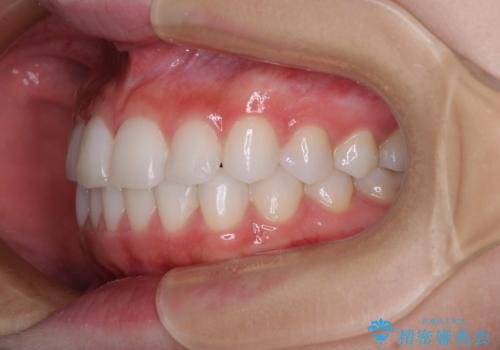

矯正治療は8ヶ月ほどで終了し、速やかに虫歯治療に移行することができました。

保険治療で用いる樹脂(コンポジットレジン)で行った虫歯治療は、周辺が変色して汚くなっていましたが、下顎はセラミックインレーで審美的に、上顎はPGAインレーで歯に負担の少ない治療を行うことができました。

- 歯並びと虫歯をきれいにしたいとのことで来院された患者様です。